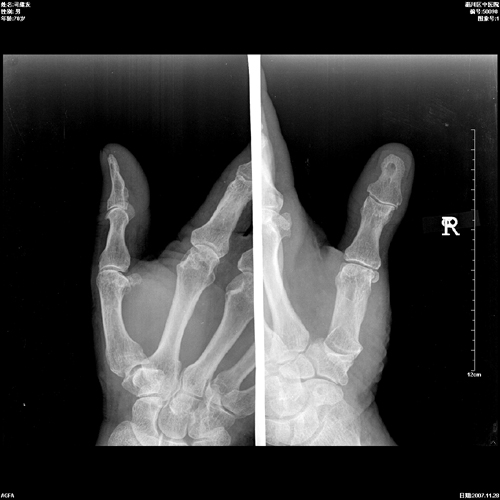

标题: X3013:男70岁,半年前拇指砸伤,近日拇指日夜疼痛。 [打印本页]

标题: X3013:男70岁,半年前拇指砸伤,近日拇指日夜疼痛。

男70岁,半年前拇指砸伤,近日拇指日夜疼痛。

植入性骨囊肿又称外伤性上皮植入性骨囊肿与创伤有关,病变多发生在末节指骨,病人都有数年以上的外伤史,手指软组织砸伤后,使小片上皮断离,并埋藏于皮下,而后逐渐移植于骨组织内,长时间增殖,生长,形成上皮样骨囊肿。

结合本例外伤史及征象,考虑上皮植入性囊肿可能性大。